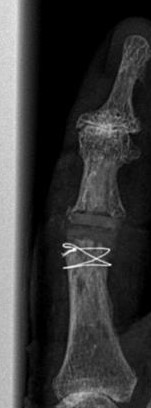

Blickfang ist hier das x-förmige Implantat zur Versteifung eines schmerzhaften und ehemals deformierten Endgelenkes.

Im Mittelgelenk fällt ein flauer "Schatten" von einem Kunstgelenk aus Silikon (Silikonendoprothese) auf.